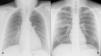

MethodsData was collected for patients who had previously undergone a chest radiograph and digital tomosynthesis due to suspected COVID-19 pneumonia. The gold standard consisted of the readings of two expert radiologists who assessed the presence and distribution of COVID-19 pneumonia on the images. Six medical students, two radiology trainees, and two other expert thoracic radiologists participated as additional readers. Two radiograph readings and a third supported by the AI Thoracic Care Suite tool were performed. COVID-19 pneumonia distribution and probability were assessed along with the contribution made by AI. Agreement and diagnostic performance were analysed.

ResultsThe sample consisted of 113 cases, of which 56 displayed lung opacities, 52.2% were female, and the mean age was 50.70±14.9. Agreement with the gold standard differed between students, trainees, and radiologists. There was a non-significant improvement for four of the six students when AI was used. The use of AI by students did not improve the COVID-19 pneumonia diagnostic performance but it did reduce the difference in diagnostic performance with the more expert radiologists. Furthermore, it had more influence on the interpretation of mild pneumonia than severe pneumonia and normal radiograph findings. AI resolved more doubts than it generated, especially among students (31.30 vs 8.32%), followed by trainees (14.45 vs 5.7%) and radiologists (10.05% vs 6.15%).